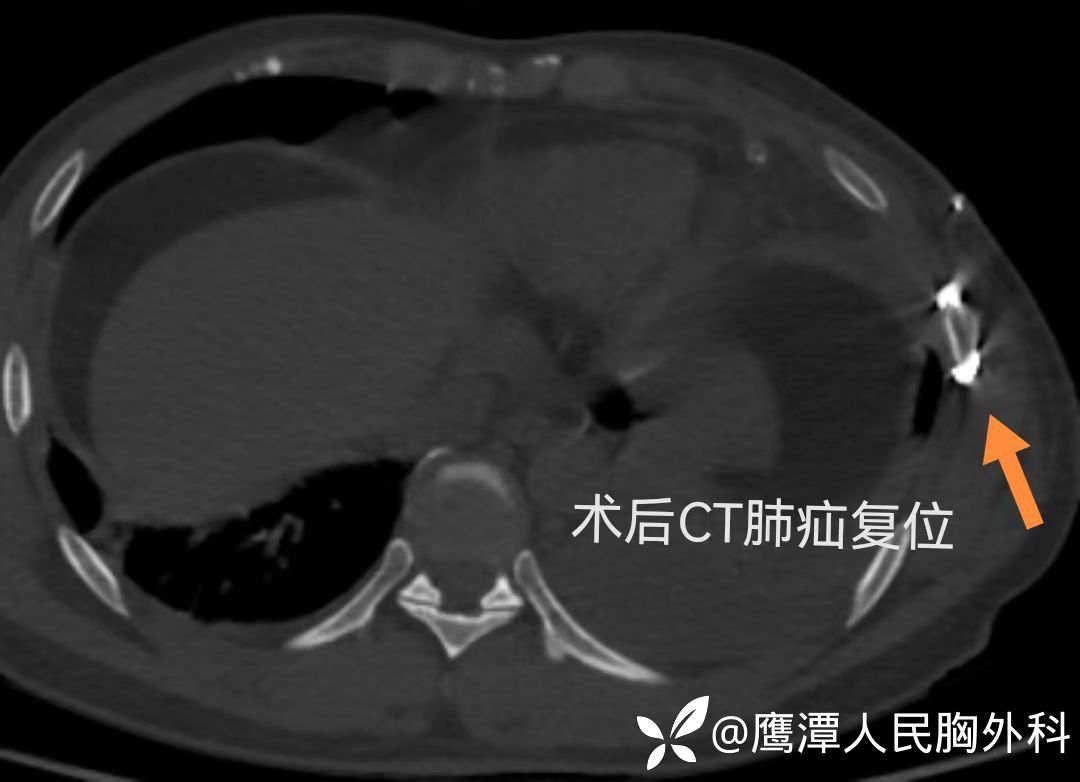

术后患者恢复良好,术后第一天疼痛明显减轻,咳嗽有力,复查胸片及胸部CT未见肺疝复发,术后第三天拔除胸腔引流管。

术后复查胸部CT图片